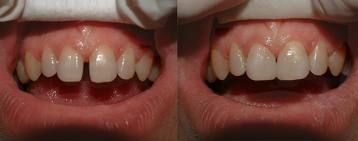

Consultatie+detartraj+periaj+airflow la numai 50RON

Va oferim un pachet de consultatie, plan de tratament, detartraj,periaj profesional si airflow la numai 50 RON in loc de 150 RON. Oferta de albire dentara este valabila numai luna Aprilie. Pentru detalii va rugam sa sunati la numarul de telefon...